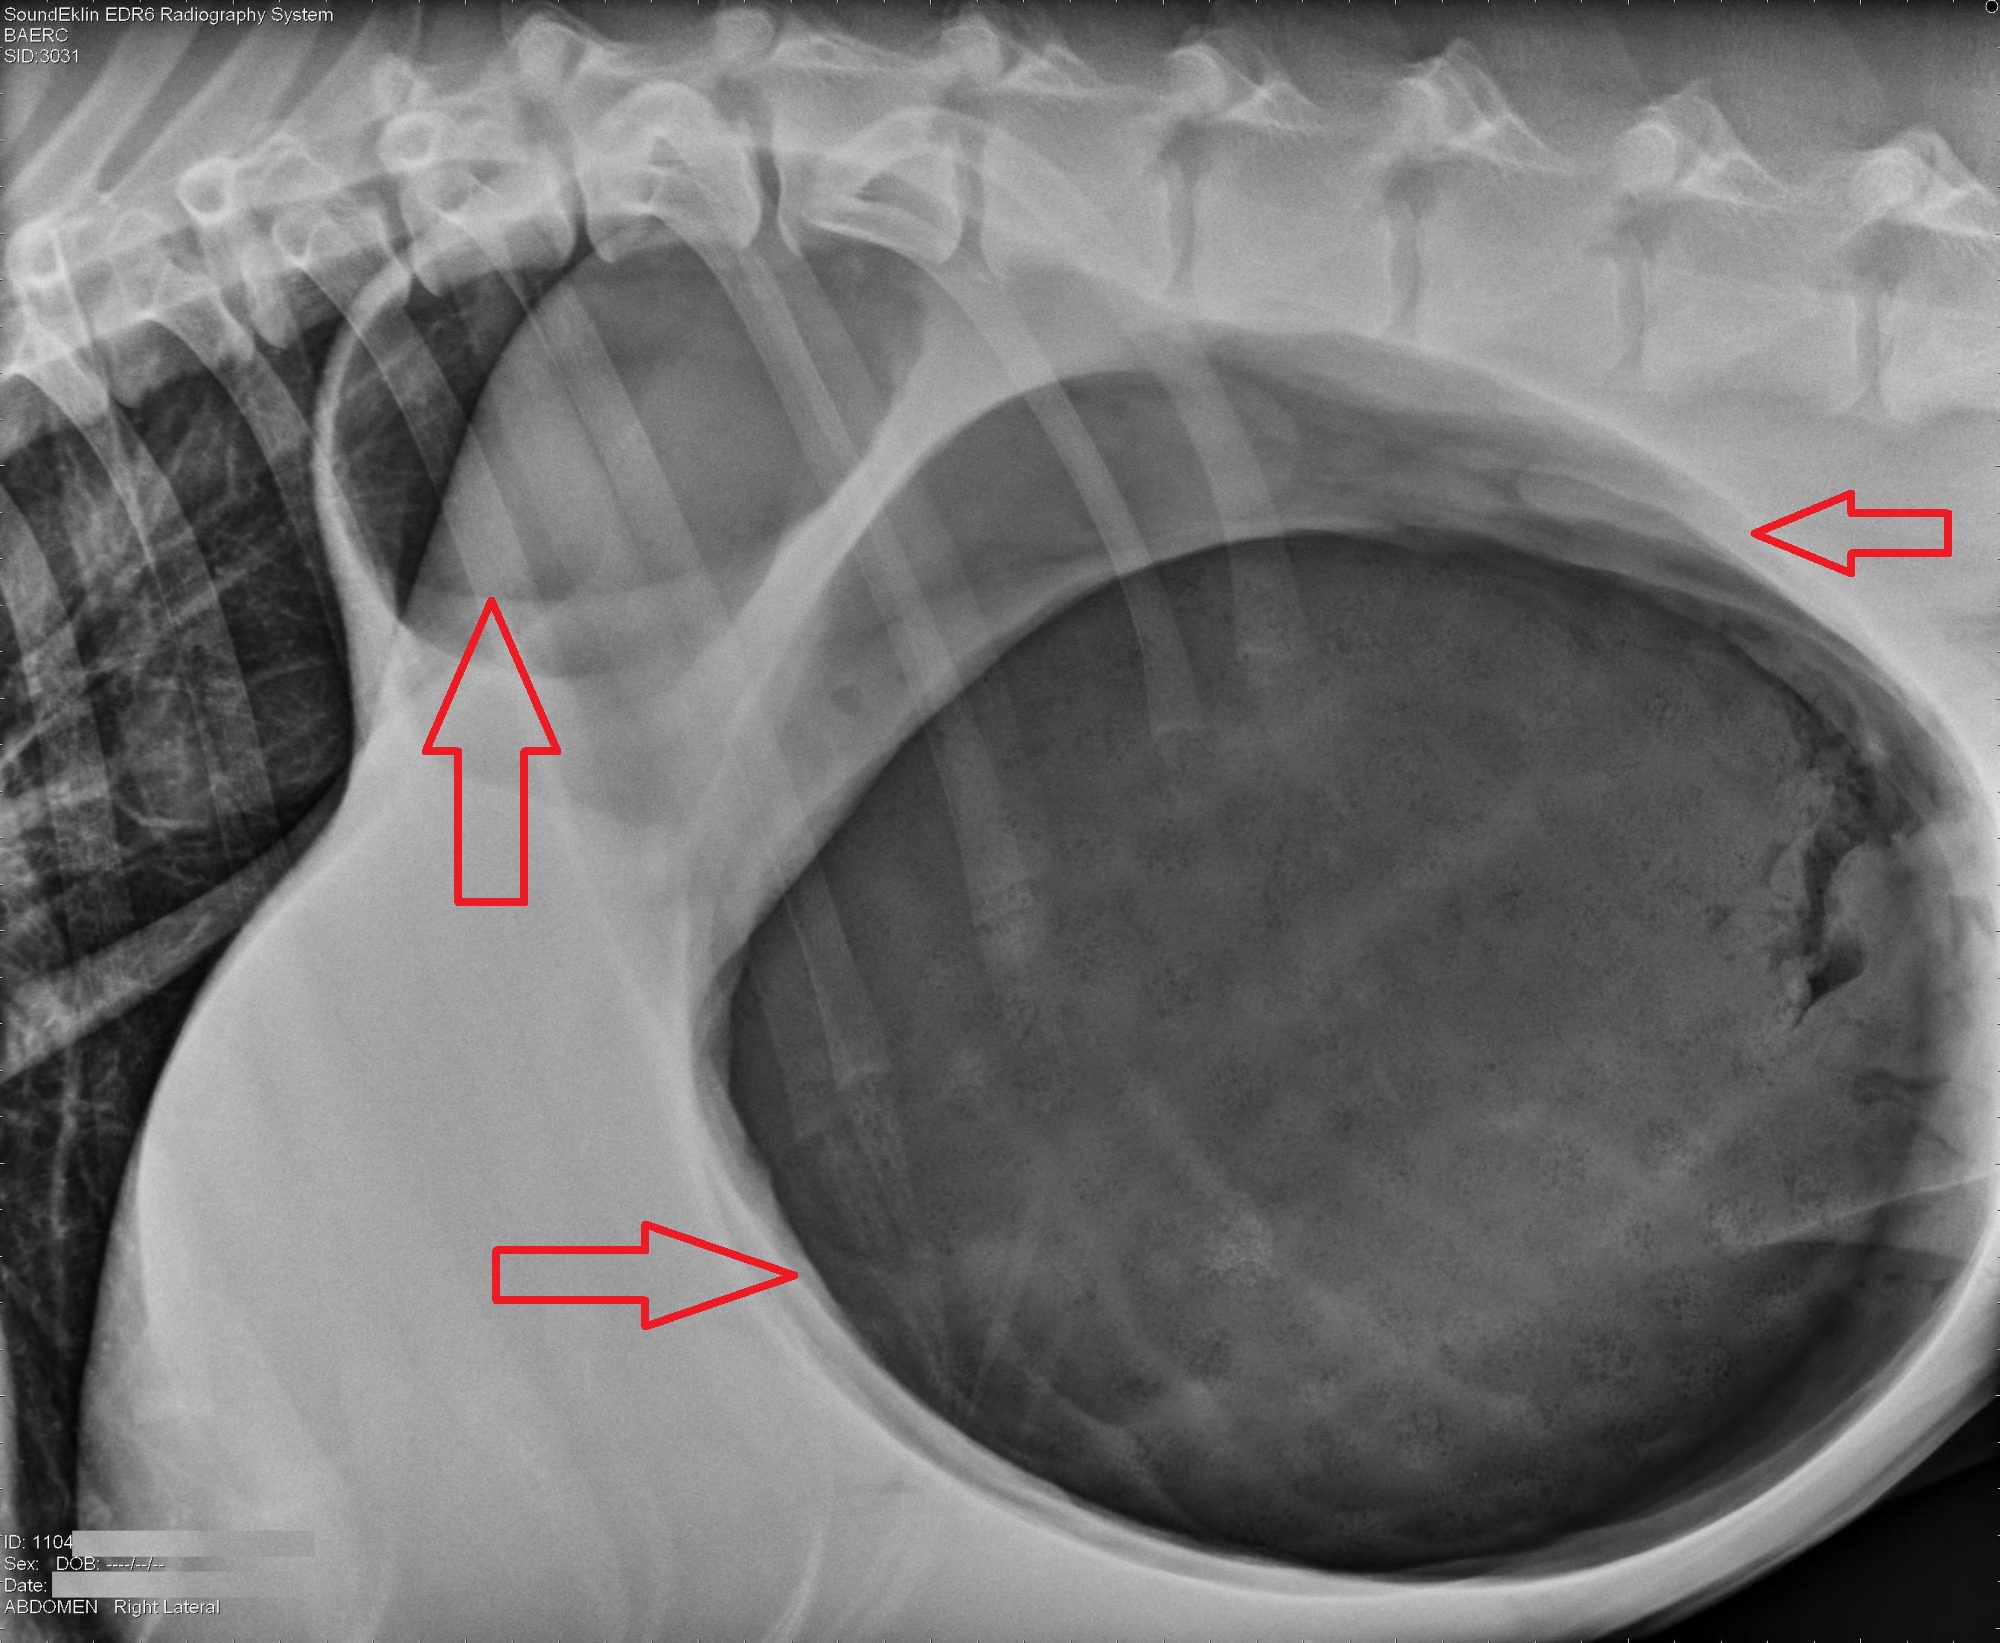

What You Need To Know About "bloat" | Dr Phil Zeltzman’s Blog

www.drphilzeltzman.com gdv ray bubble double bloat zeltzman phil dr example classic